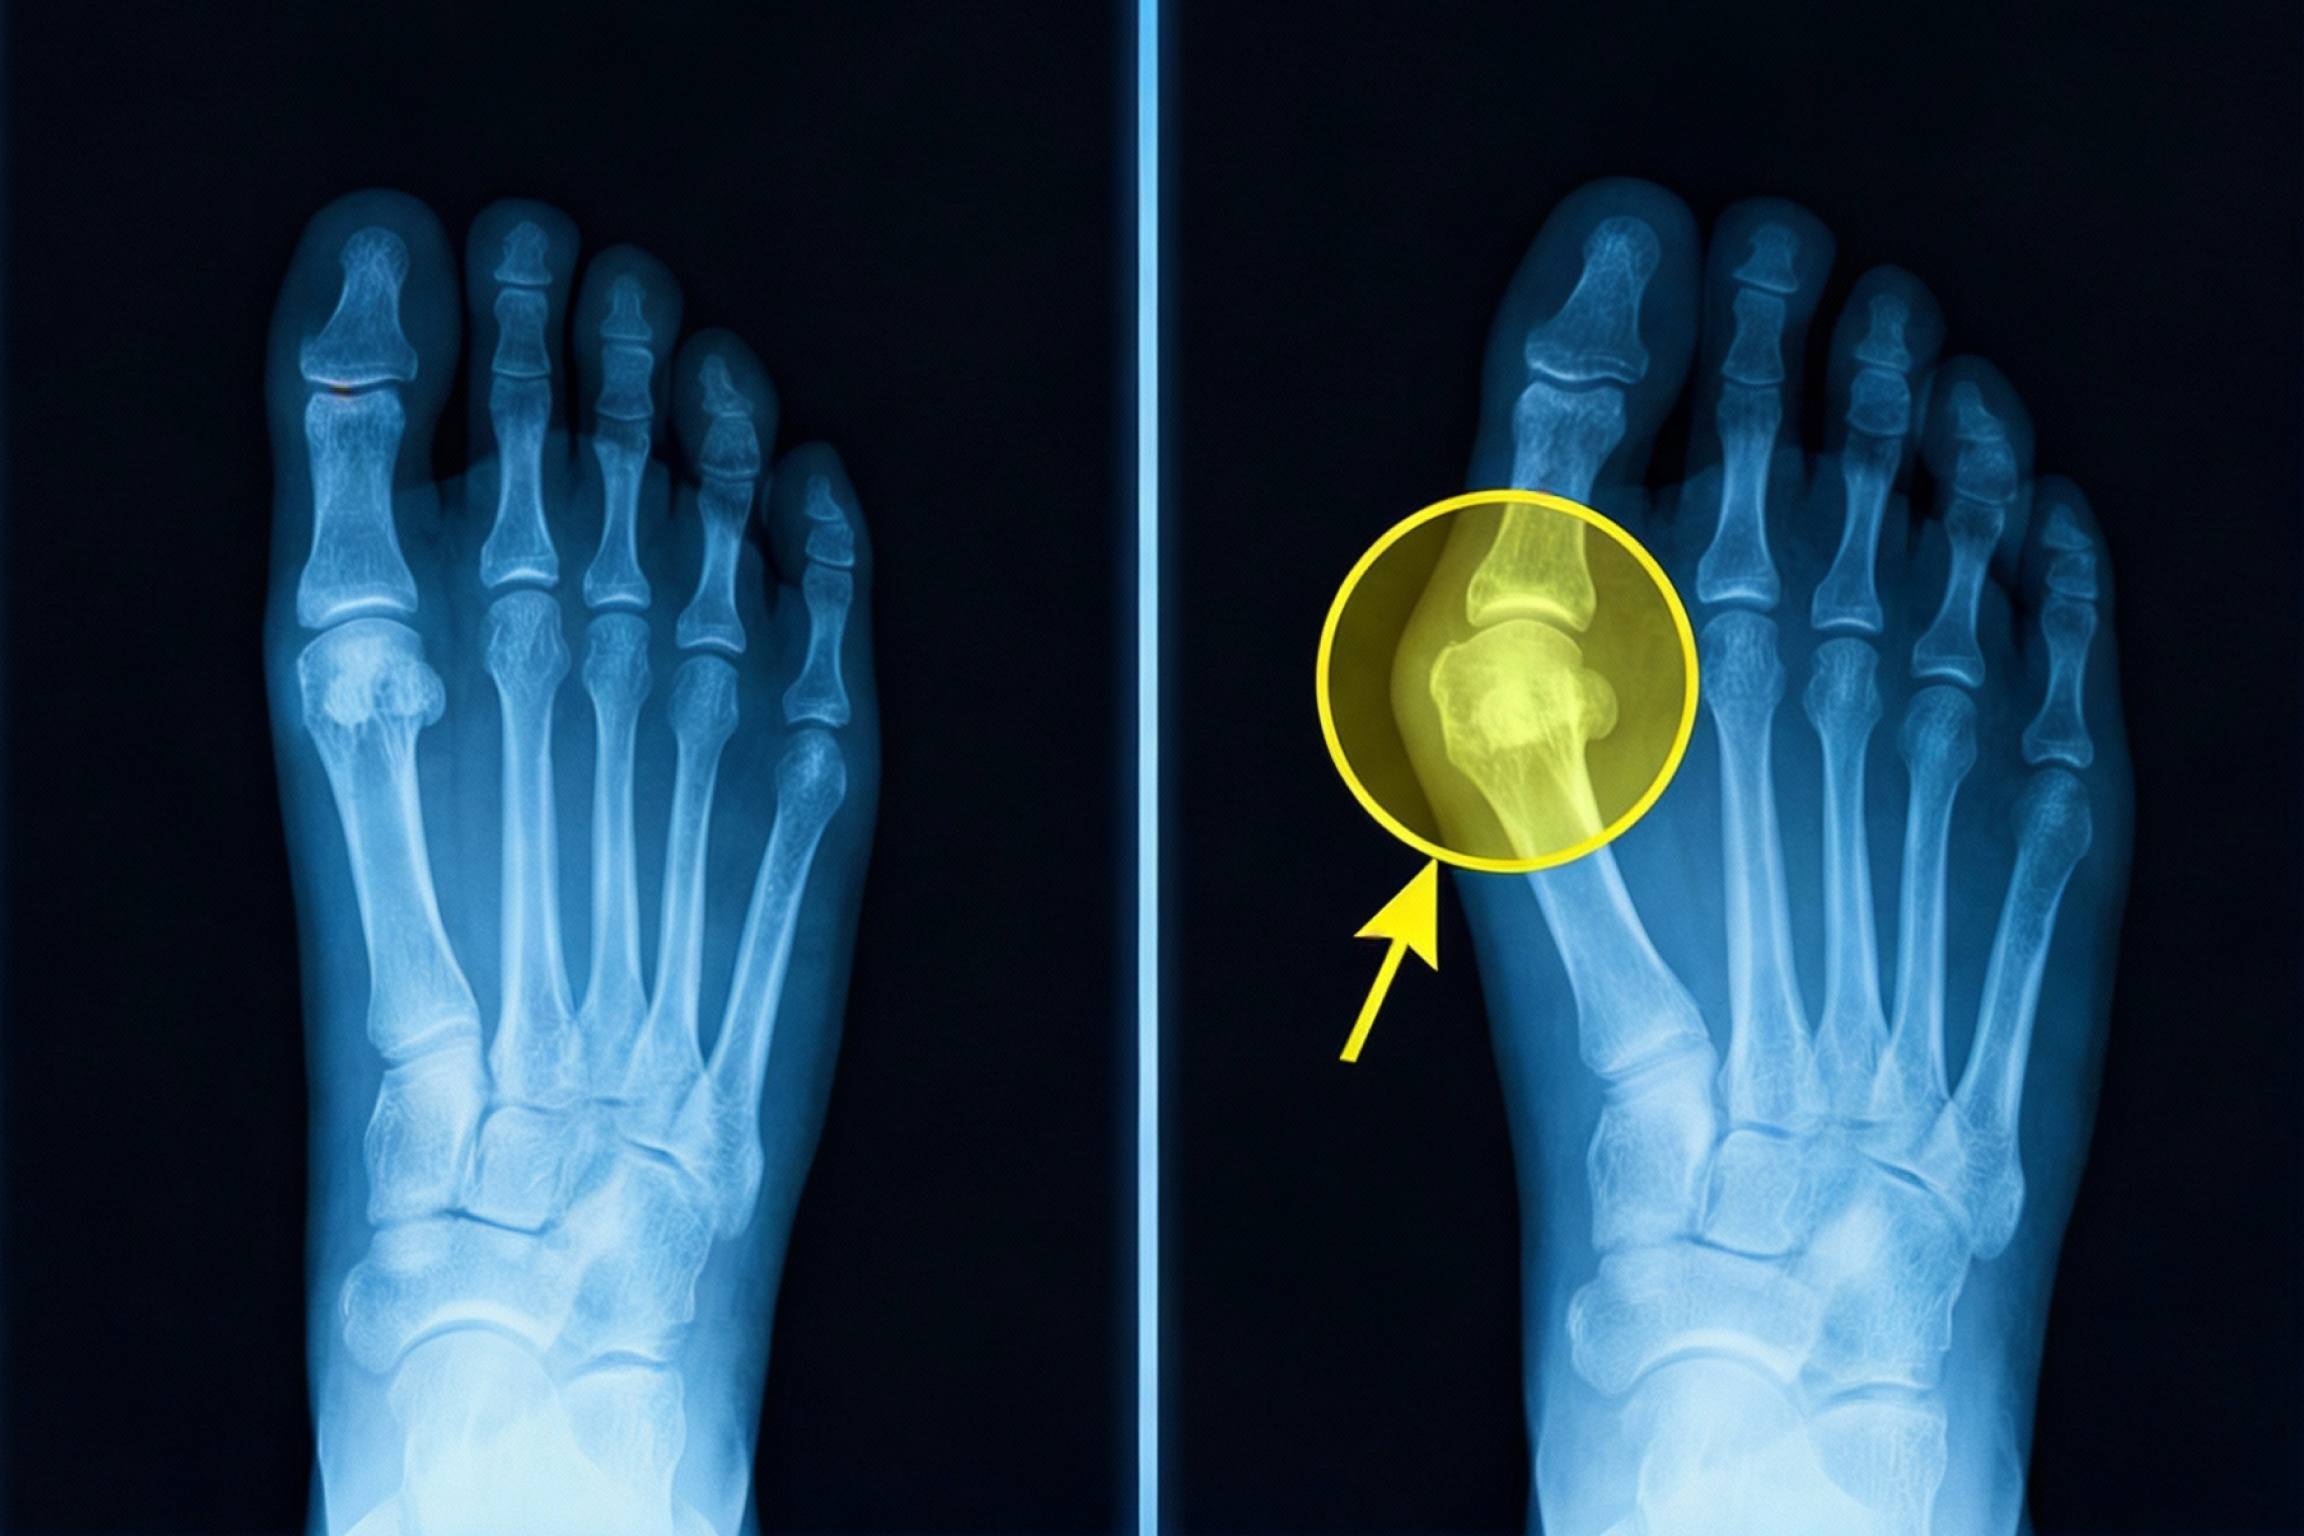

That painful bunion "bump" you see? That's not your problem.

95% of bunion sufferers are treating the wrong thing.

Your toe starts drifting out of alignment. The joint gets pushed out of its socket. The "bump" forms and keeps growing.